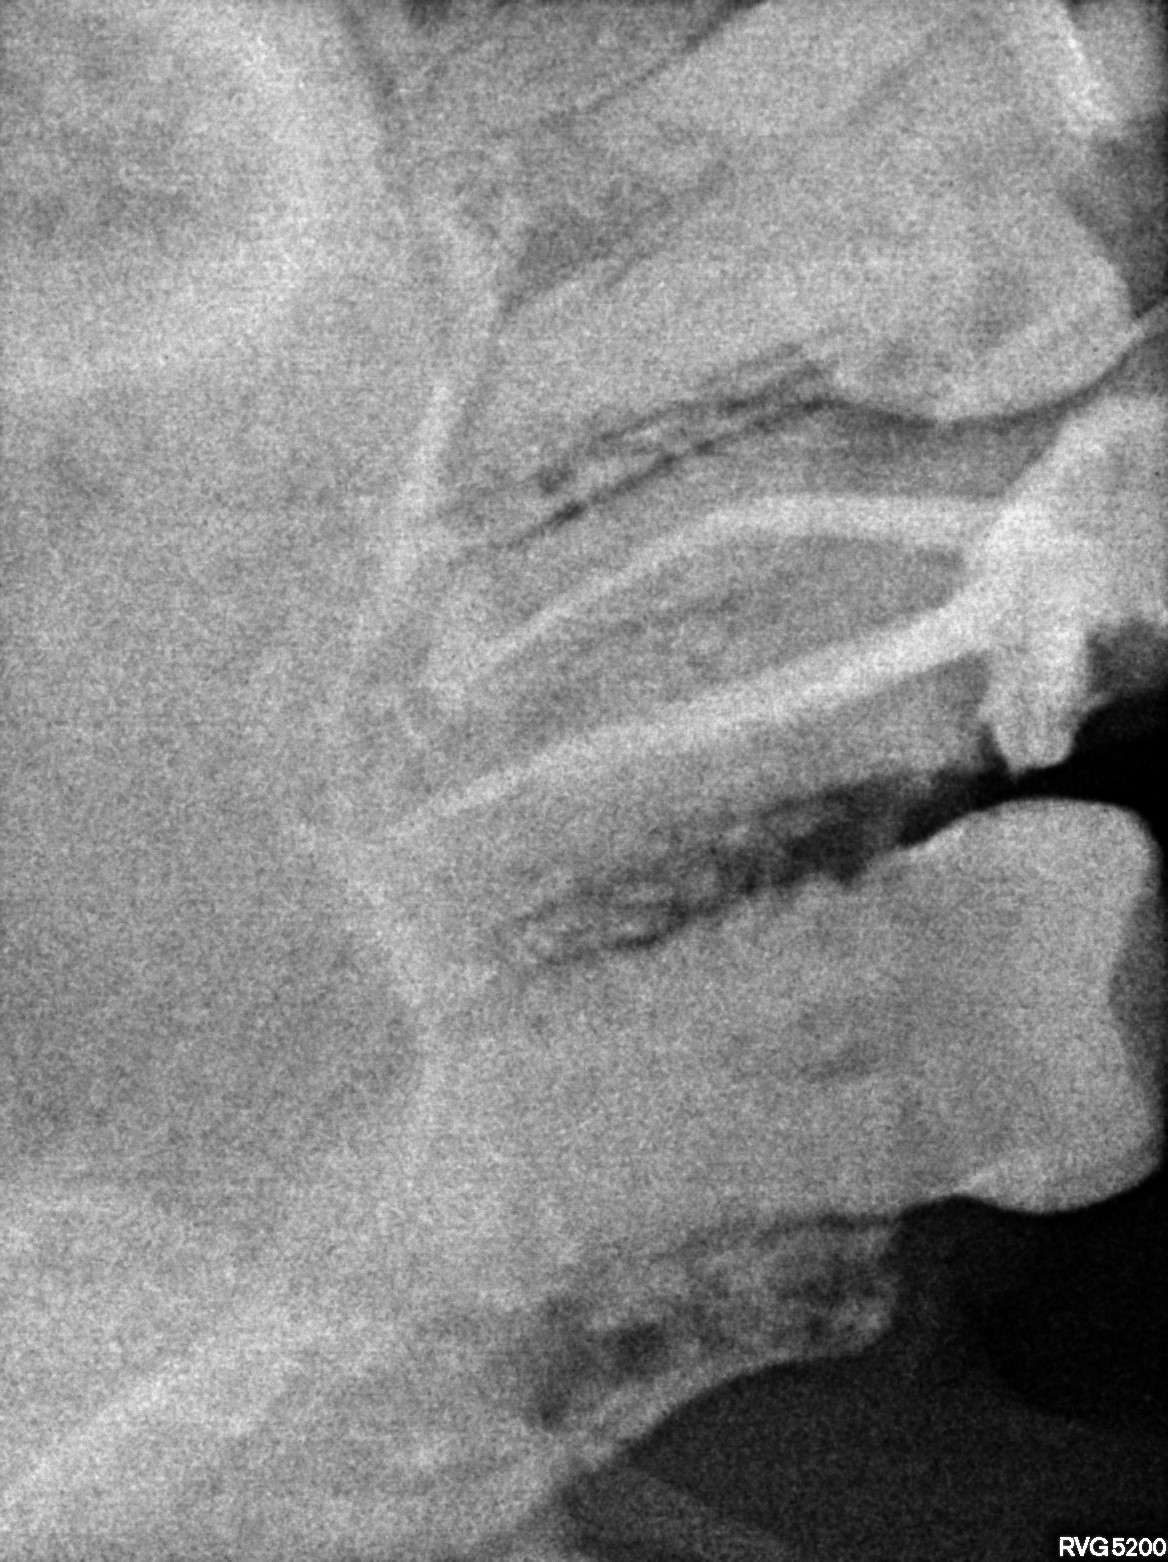

Dental Radiographs FHIR: DocumentReference · LOINC 24641-7

xray_1772726444_0.jpg

24641-7